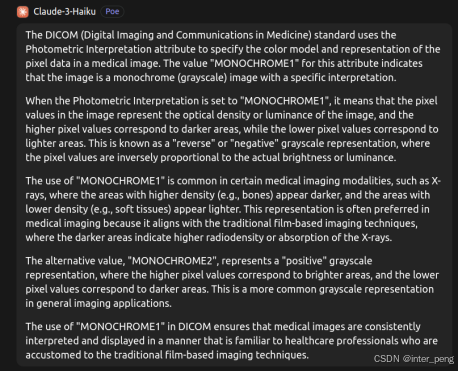

但后来通过询问GPT, 才了解到,这其实可能是故意为之的.

GPT给出的回答是:对于某一些传统的显示设备,或专家,他们更习惯来看,就是用白色代表密度低,黑色代表密度高的片子. 因此,在拍摄的时候,设备才会这样而为之.